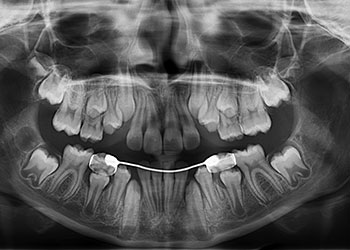

IMÁGENES 2D

Alta resolución con equipos de última generación

Rx Extraorales e Intraorales